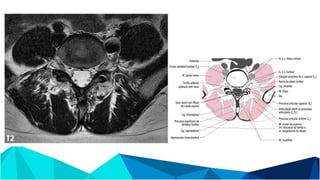

ANATOMIA

- Raízes motoras são ventrais às raízes sensitivas em todos os níveis

- Até C7 o pedículo sai acima da vértebra correspondente